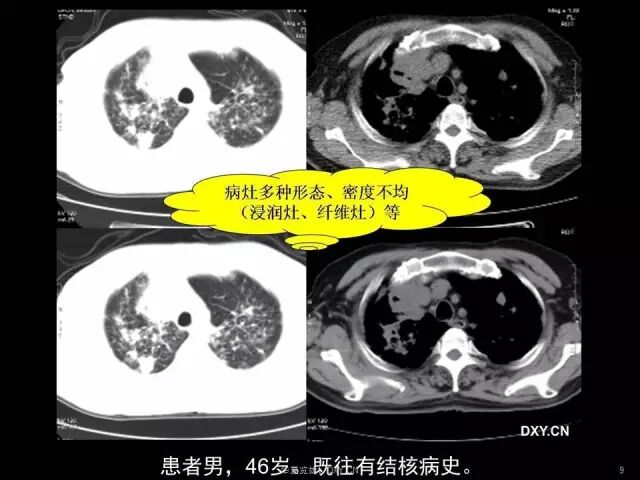

肺炎、肺癌、肺结核在影像学上的征象往往千变万化。